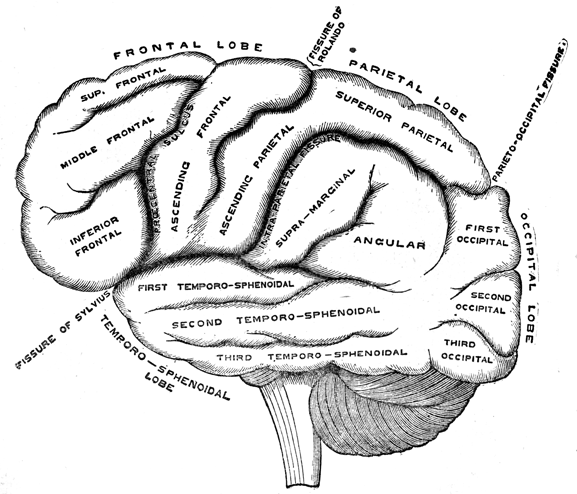

Chapter II—Structure of the Brain.

of the brain in the head, illustrated and described—The cerebrum,

cerebellum, and tentorium—Interior view of the base of the skull—Bones

of the head illustrated—Division of the brain into lobes

and convolutions, with illustration—Frontal, middle, parietal,

tempero-sphenoidal, and occipital—Anatomical plan or grouping of

convolutions differs from their actual appearance—View of the superior

surface illustrated—Difference between the irregular convolutions